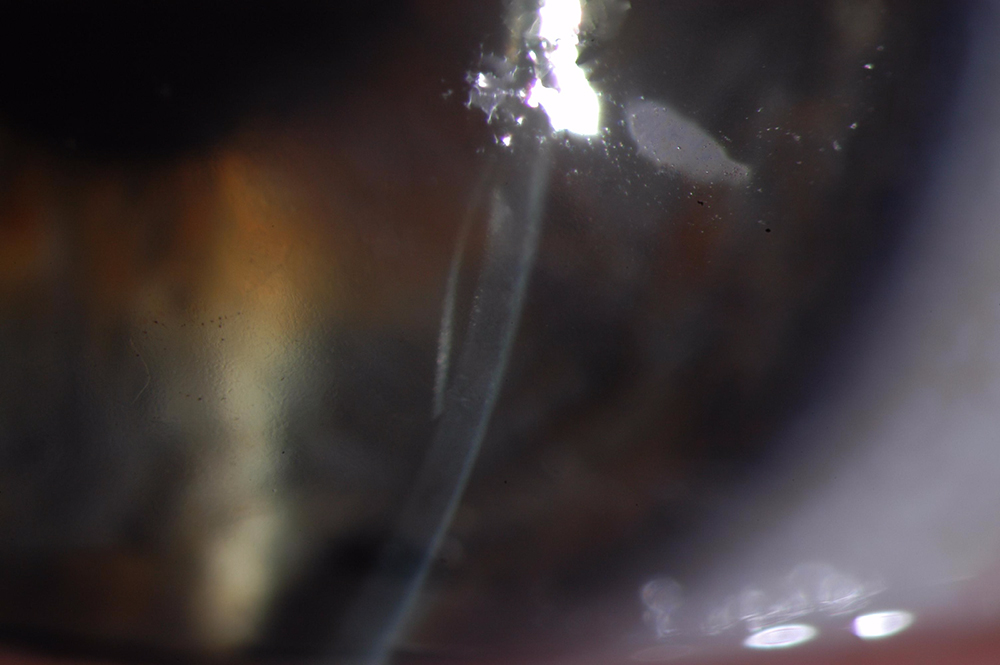

This image above was taken with an office examining scope. Special lighting techniques allow visualization of the DMEK edge.

Here is another special lighting technique to see the edge of the DMEK on this same eye.